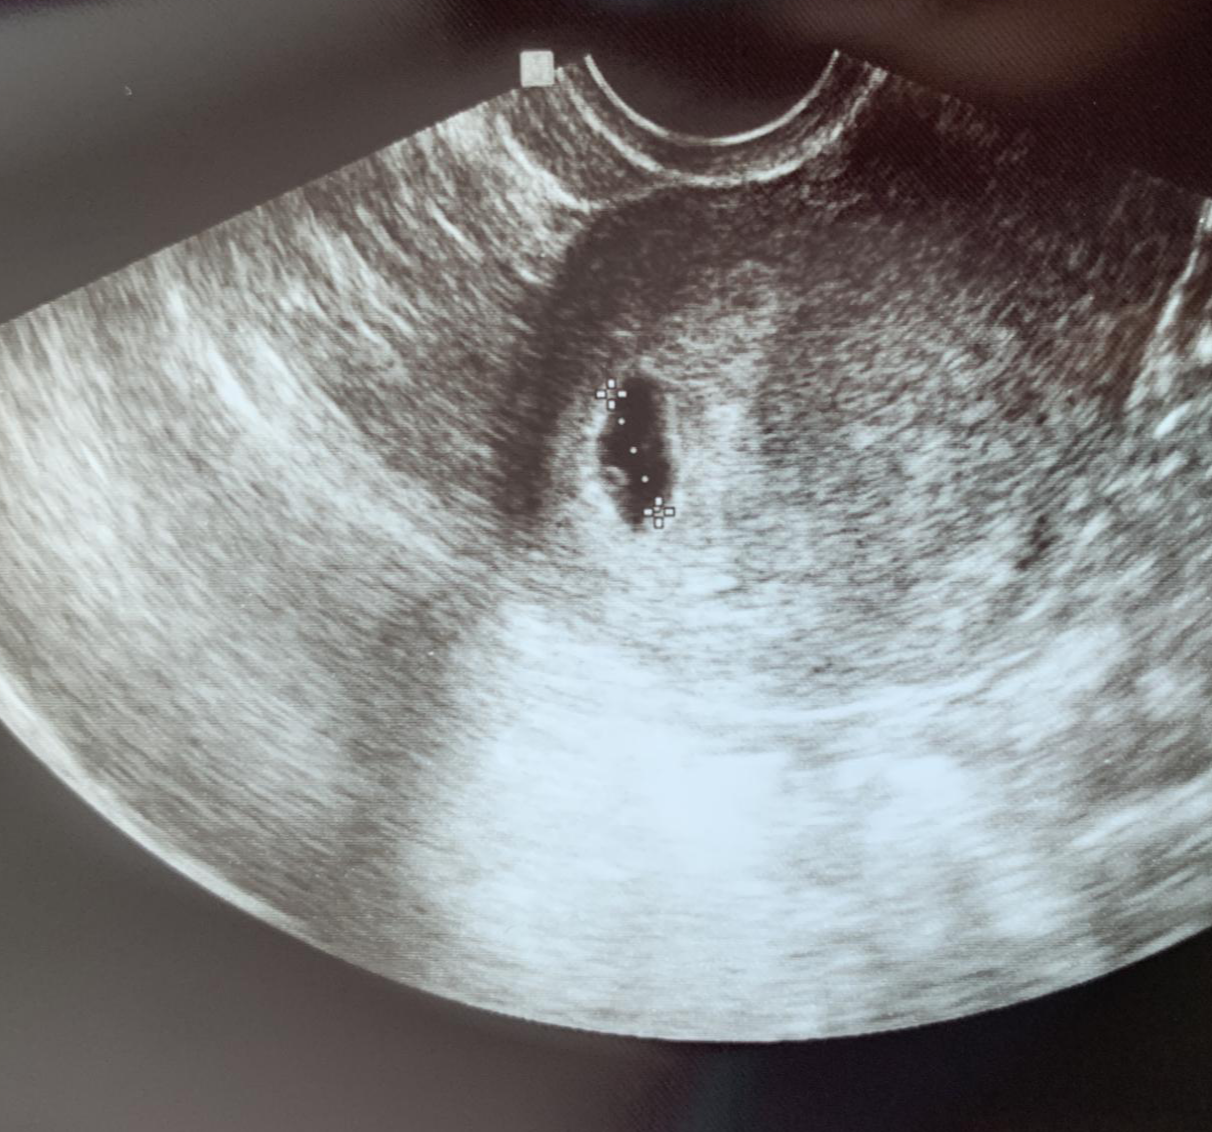

피검사 이후 초음파로 아기집을 확인해야만 “임신입니다” 소리를 공식적으로 들을 수 있고 임신임을 증명해주는 임신 확인서류를 받을 수 있다. 배아에서 태아가 되는 순간이다. 떨리는 마음으로 병원에 도착했고 긴장되는 가운데 아내가 초음파실로 들어갔다. 얼마 지나지 않아 “남편 분 들어오세요”라는 말에 처음 초음파실에 들어가 봤고 역사적인 순간을 만났다. 아기집과 난황이 제 위치에 건강히 자리 잡고 있다는 것이다. 아내의 손을 잡고 우린 서로 말없이 안도했고 소리없이 환호했다. 예쁨아 안녕? 흐흐흫하하하흫하. 기대하던 말을 해주는 의사 선생님은 날개 없는 천사로 보인다.

첫 초음파 사진이다.(임신4주), 아기집과 난황이 보인다. 예쁨아 안녕?? 초음파 사진은 그 자리에서 바로 출력해서 준다. 실제 모니터로 볼 때보다 출력물로 보는 게 조금 더 잘 보이는 건 기분 탓일까. 그리고 한 가지 더 대박인 것은 산부인과에서 임신 어플을 지원해준다. 그 어플에는 초음파 영상이 담기는데 진료비 결제 후 확인하니 벌써 업데이트가 되어 있더라. 세상 진짜 좋다.